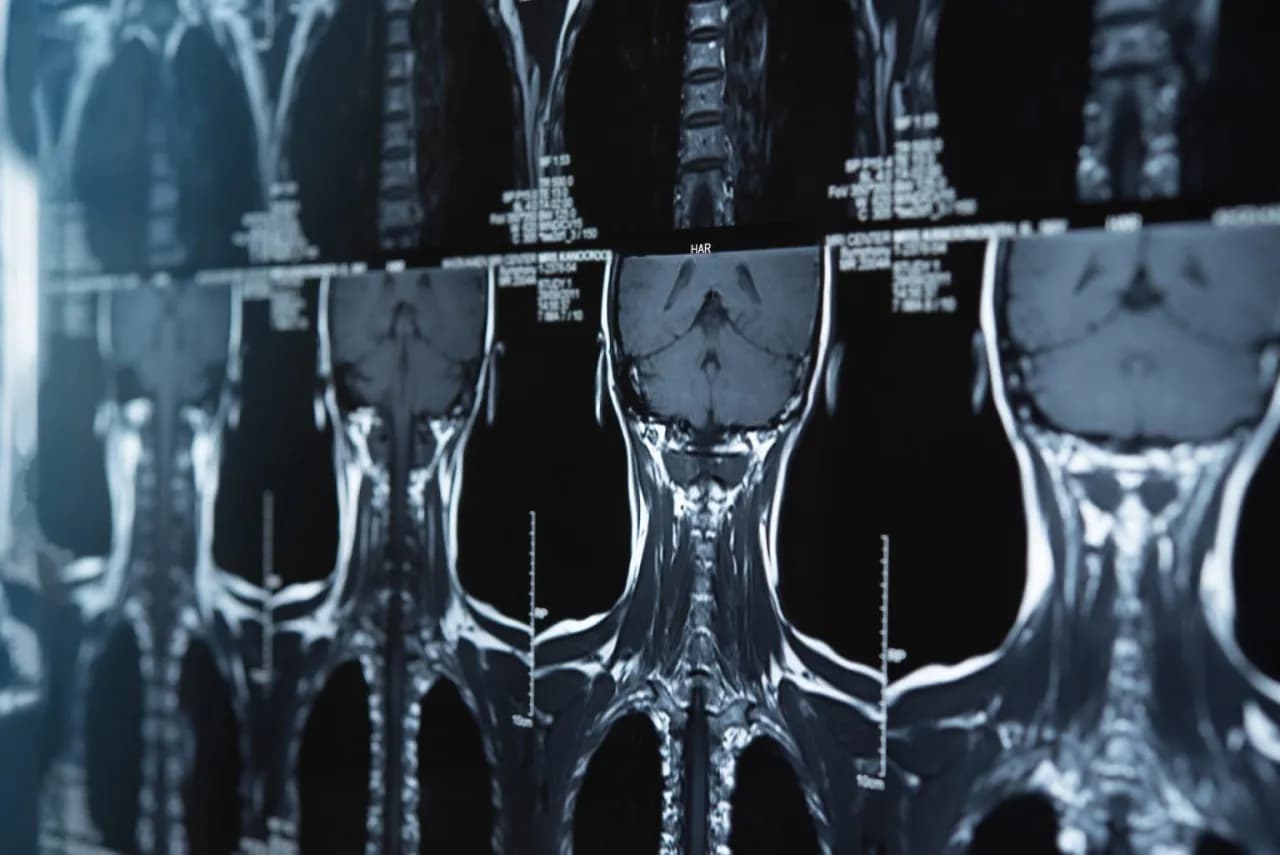

Rezonans odcinka szyjnego ile trwa? Poznaj czas badania i szczegóły